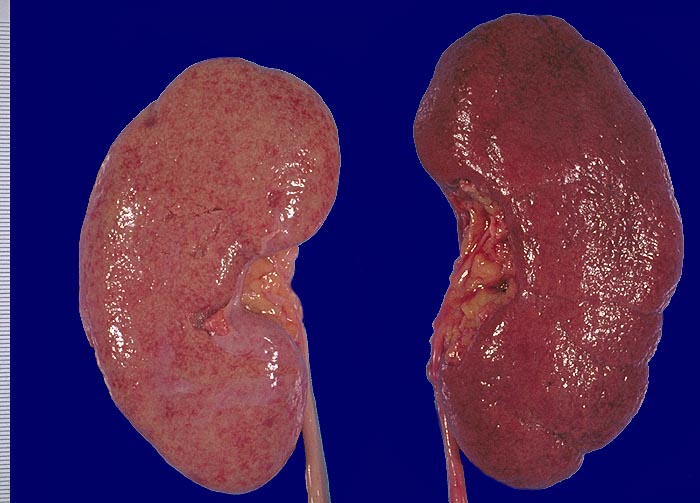

PathoPic – image database / PathoPic ID 1899 - Noduläre Glomerulosklerose links, Arteriolosklerose rechts

Noduläre Glomerulosklerose links, Arteriolosklerose rechts

Links: Diabetikerniere mit fein granulierter Nierenoberfläche und gelblich-roter Farbe.

Rechts: Niere bei arterieller Hypertonie stärker rot und ebenfalls fein granuliert.

Linke Niere: Diabetes mellitus Typ I. Fortgeschrittene Niereninsuffizienz.

Die diabetische Niere ist im allgemeinen vergrössert, die Oberfläche granuliert und die Konsistenz derb. Bei schwerer Atherosklerose und fortgeschrittener Niereninsuffizienz kann die Niere auch normal gross oder verkleinert sein.